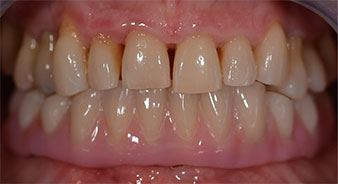

The impression and bite registration were then performed so that the dental technician could begin producing the provisional restoration immediately. This was then screwed in on the same day (Fig. 17 and 18).

Implants

Fig. 17

Fig. 18

Following the time required for the osseointegration, the final impression of the implants could be performed and the final denture produced accordingly (Fig. 19 and 20). At this point, the dentist and patient were able to decide together whether to use a ceramic or acrylic veneer and a zirconium or metal framework. In this case, Dr. Pascu’s team decided on an acrylic veneer based on the unclear prognosis for the maxillary dentition and the fact that tooth 24 is elongated. This type of veneer is generally considerably easier to adapt and can thus be subsequently altered to reflect the new situation in the maxilla.

Osseointegration

Fig. 19

Fig. 20